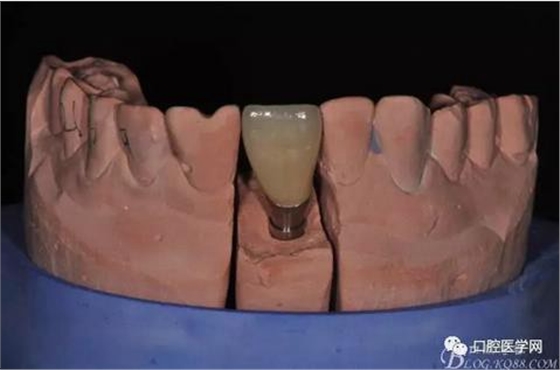

圖14 烤瓷冠模型唇側(cè)照

圖15 烤瓷冠模型舌側(cè)照